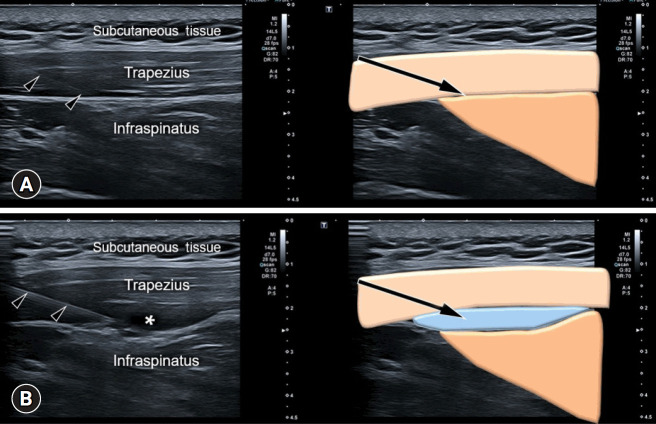

Myofascial pain syndrome (MPS) is a common musculoskeletal disorder characterized by muscle pain, tenderness, and trigger points. Ultrasonography has emerged as a key tool for diagnosing and treating MPS owing to its ability to provide precise, minimally invasive guidance. This review discusses the use of ultrasonography in various approaches to evaluate and manage MPS. Studies have shown that shear-wave sonoelastography can effectively assess muscle elasticity and offer insights into trapezius stiffness in patients with MPS. Ultrasound-guided interfascial hydrodissection, especially with visual feedback, has demonstrated effectiveness in treating trapezius MPS. Similarly, ultrasound-guided rhomboid interfascial plane blocks and perimysium dissection for posterior shoulder MPS have significantly reduced pain and improved quality of life. The combination of extracorporeal shockwave therapy with ultrasound-guided lidocaine injections has been particularly successful in reducing pain and stiffness in trapezius MPS. Research regarding various guided injections, including dry needling, interfascial plane blocks, and fascial hydrodissection, emphasizes the importance of ultrasonography for accuracy and safety. Additionally, ultrasound-guided delivery of local anesthetics and steroids to the quadratus lumborum muscle has shown lasting pain relief over a 6-month period. Overall, these findings highlight the pivotal role of ultrasonography in the assessment and treatment of MPS.